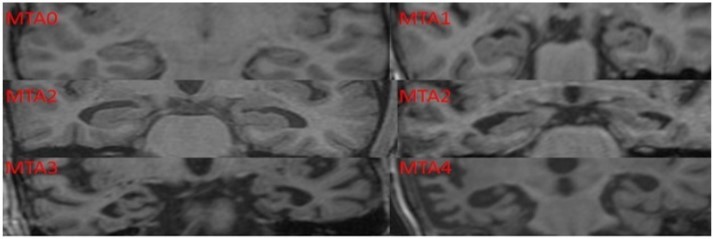

Scheltens Visual Rating of Medial Temporal Lobe Atrophy: The visual rating of MTLA was done using this scale5by obtaining T1 weighted coronal section image on MRI scan of the brain. This rating does not require any special radiological training and can be done easily using hard copies of T1 weighted coronal sections of the brain

MRI. It has a diagnostic accuracy of over 80% in diagnosing dementia of Alzheimer’s type (Table 1).

Radiology Protocol

MTLA was assessed using a template based on Scheltens Visual Rating Scale (Figure 1). MRI scans were done using 1.5 Tesla Magnetic Resonance (Megnatom Symphony 1.5T scanner). T1 weighted Coronal sections were used for rating MTLA.

Figure 1.Scheltens Visual Rating Scale used in the current study to assess the medial temporal lobe atrophy rating scores.

Scheltens Visual Rating Scale used in the current study to assess the medial temporal lobe atrophy rating scores.